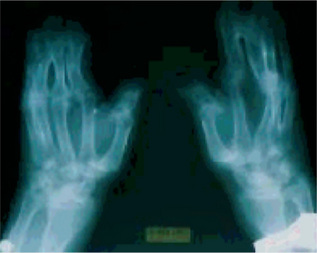

This dysplasia is characterized by a short-limbed stature. There is hypoplasia or absence of the lateral portion of the clavicles, and hypoplasia of the terminal phalanges of the digits (termed acro-osteolysis), leading to short, stubby hands with large finger nails. The skull has widened sutures and persistent open fontanels, even into adulthood. The mandible is small, and the angle of the mandible is obtuse, leading to a very small chin. The nose is protuberant. The teeth are delayed in appearance and disordered when present.

Radiographs show generalized osteosclerosis. The medullary canal is always present, but it is small and irregular. The sclerotic bone has a propensity to fracture, with fractures generally occurring in the lower extremities. Bone formation and resorption are simultaneously diminished. MRI studies have shown the cortex to be of normal thickness, whereas the space within the medullary canal was limited as a result of the increase in trabecular bone. Bone scan reveals increased uptake.